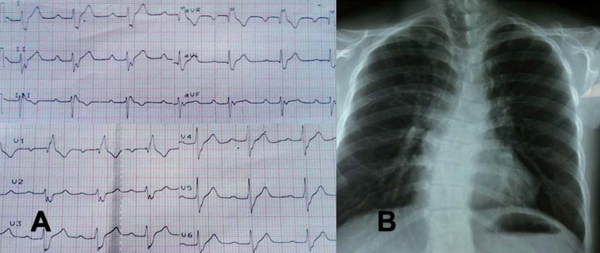

En el electrocardiograma destaca PR prolongado, bloqueo completo de rama derecha y hemibloqueo anterior izquierdo. En la radiografía de tórax se evidencia hiperflujo pulmonar y escoliosis de la columna dorsal con concavidad izquierda (Figura 2). El ecocardiograma transtorácico reportó comunicación interauricular tipo ostium primum de 22 mm, comunicación interventricular de 15 mm totalmente ocluida por velo septal tricuspídeo convirtiendo un canal AV intermedio en un canal AV parcial e hipertensión pulmonar leve.

Figura 2: A. Electrocardiograma, aVR, aVL y aVF registradas a 1mV/5mm: Ritmo sinusal, 75 lpm, Eje QRS - 90°, intervalo PR de 240 ms, complejo QRS de 120 ms con morfología de bloqueo completo de rama derecha y hemibloqueo anterior izquierdo. B. Radiografía A-P: Situs solitus, índice cardiotorácico de 0,48, cono de arteria pulmonar prominente, aumento de la trama vascular, escoliosis de la columna dorsal.